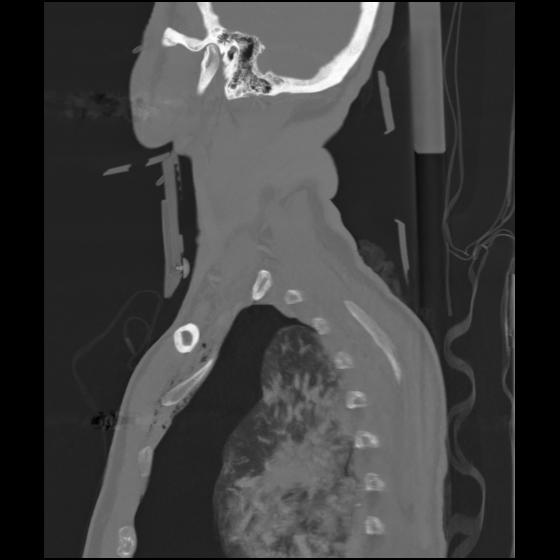

24 ANGIO,CE,Sag-MIP,5.000,ANGIO,Sag-MIP,